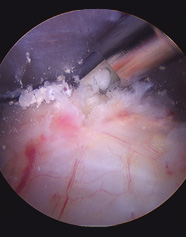

Abb 4; Operative (arthroskopische) Ausräumung des Kalkes

Ich führe ausschließlich die Kalkausräumung ausschließlich mit der sogenannten der arthroskopischen Technik durch (Bedeutung: arthron [altgriechisch] = Gelenk; skopeĩn [griechisch] = betrachten). Dabei wird über einen wenige Millimeter langen Stich durch die Haut eine ganz dünne Stabkamera in den Schleimbeutel der Schulter eingeführt. Über einen zweiten kleinen Stich wird ebenfalls mit einem stabförmigen Instrument das Kalkdepot in der Sehne aufgesucht und unter permanenter Sicht gezielt ausgeräumt (Abb 4). Je nach Umfang der Kalkablagerungen können weitere kleine Hautstiche notwendig sein. Der Vorteil dieser Methode liegt darin, dass trotz minimaler Verletzung des Gewebes einerseits ein ungezieltes "blindes" Verletzen der Sehnen vermieden, und andererseits eine sichere und verlässliche Entfernung des Kalkes gewährleistet werden kann. In einigen Fällen wird am Ende der Operation ein Drainageröhrchen eingelegt um Wundsekret abzuleiten.